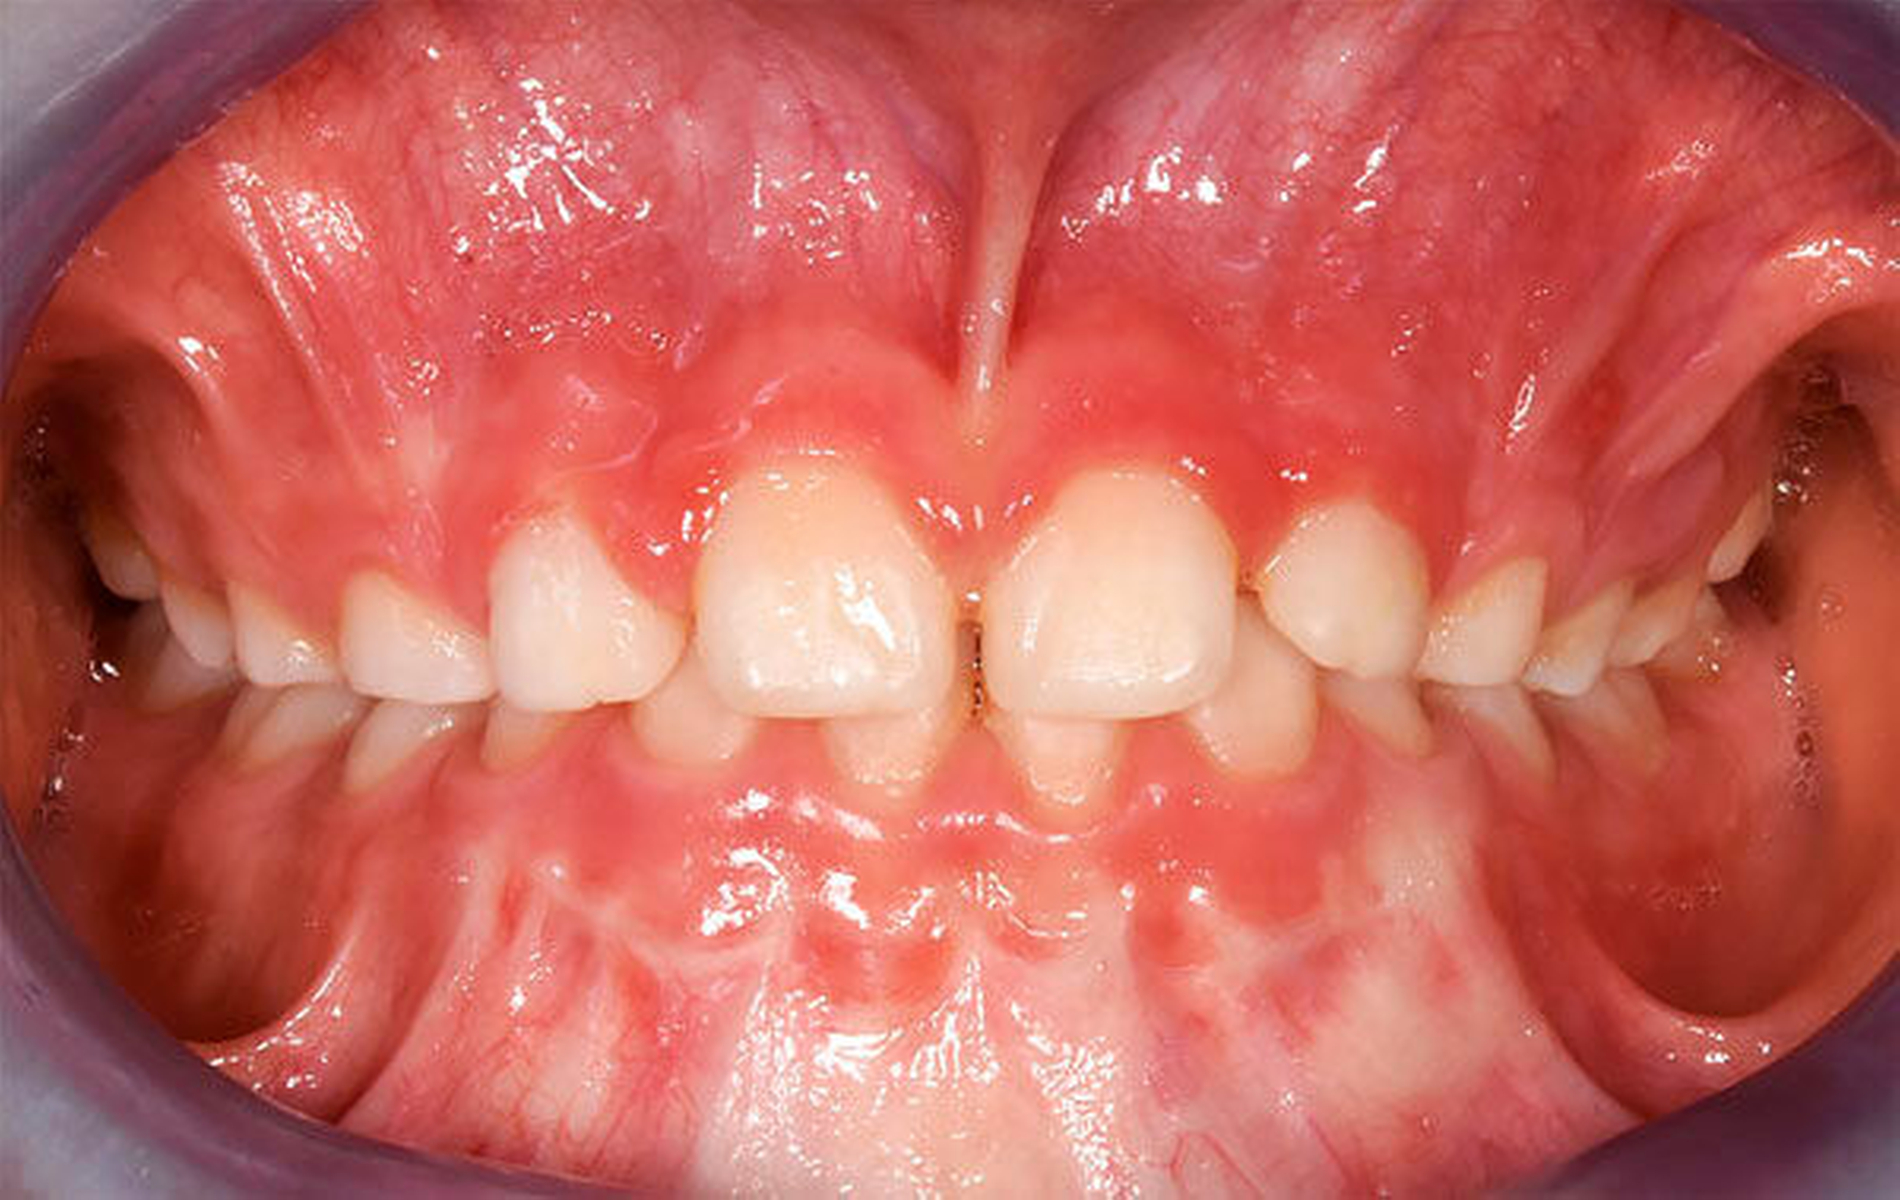

In der Gruppe des progenen Formenkreises werden Zahn- und Kieferfehlstellungen unterschiedlichster Ätiologie zusammengefasst. Diese können durch ein Missverhältnis im Wachstum beider Kiefer bedingt sein, das heißt durch Überentwicklung (Makro-/Prognathie) des Unterkiefers und/oder Unterentwicklung (Mikro-/Retrognathie) des Oberkiefers [Rakosi, 1989]. Besteht ein frontaler Kreuzbiss von Einzelzähnen oder einer ganzen Zahngruppe wird der Oberkiefer durch den Unterkiefer „eingefangen“, das heißt durch die palatinalwärts positionierten OK-Inzisiven wird das Oberkieferwachstum im Alveolarfortsatzbereich gehemmt sowie das Unterkieferwachstum „freigegeben“, da der Unterkiefer sich postnatal in sagittaler Richtung ohnehin stärker als der Oberkiefer entwickelt [Lux, 2004]. Zudem kann eine Zwangsbissführung des Unterkiefers nach ventral vorliegen [Keeling, 1998]. Diese kann zusätzlich zu einer unerwünschten Wachstumsstimulation des Unterkiefers mit nachfolgender skelettaler Manifestation führen. Mit einem therapeutisch eingestellten sicheren frontalen Überbiss (sagittal und vertikal) kann die weitere Kieferentwicklung koordinierter ablaufen (Abbildung 4). Die Anomalien des progenen Formenkreises besitzen häufig auch eine hereditäre Komponente, wobei unphysiologische Ruheweichteilbeziehungen oder Dysfunktionen den Phänotyp deutlich verstärken können. Da bei Klasse-III-Dysgnathien die skelettalen Therapieergebnisse bei frühzeitigem Behandlungsbeginn am besten sind, sollte frühzeitig mit einer kausalen Therapie begonnen werden – also sobald eine ausreichende Compliance des Patienten es zulässt, [Baccetti, 1998; Da Silva, 1998; Franci, 2004; Lang, 2001; Saadi, 2000].